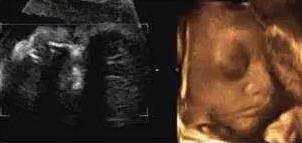

麻麻,我在咬手指哟!